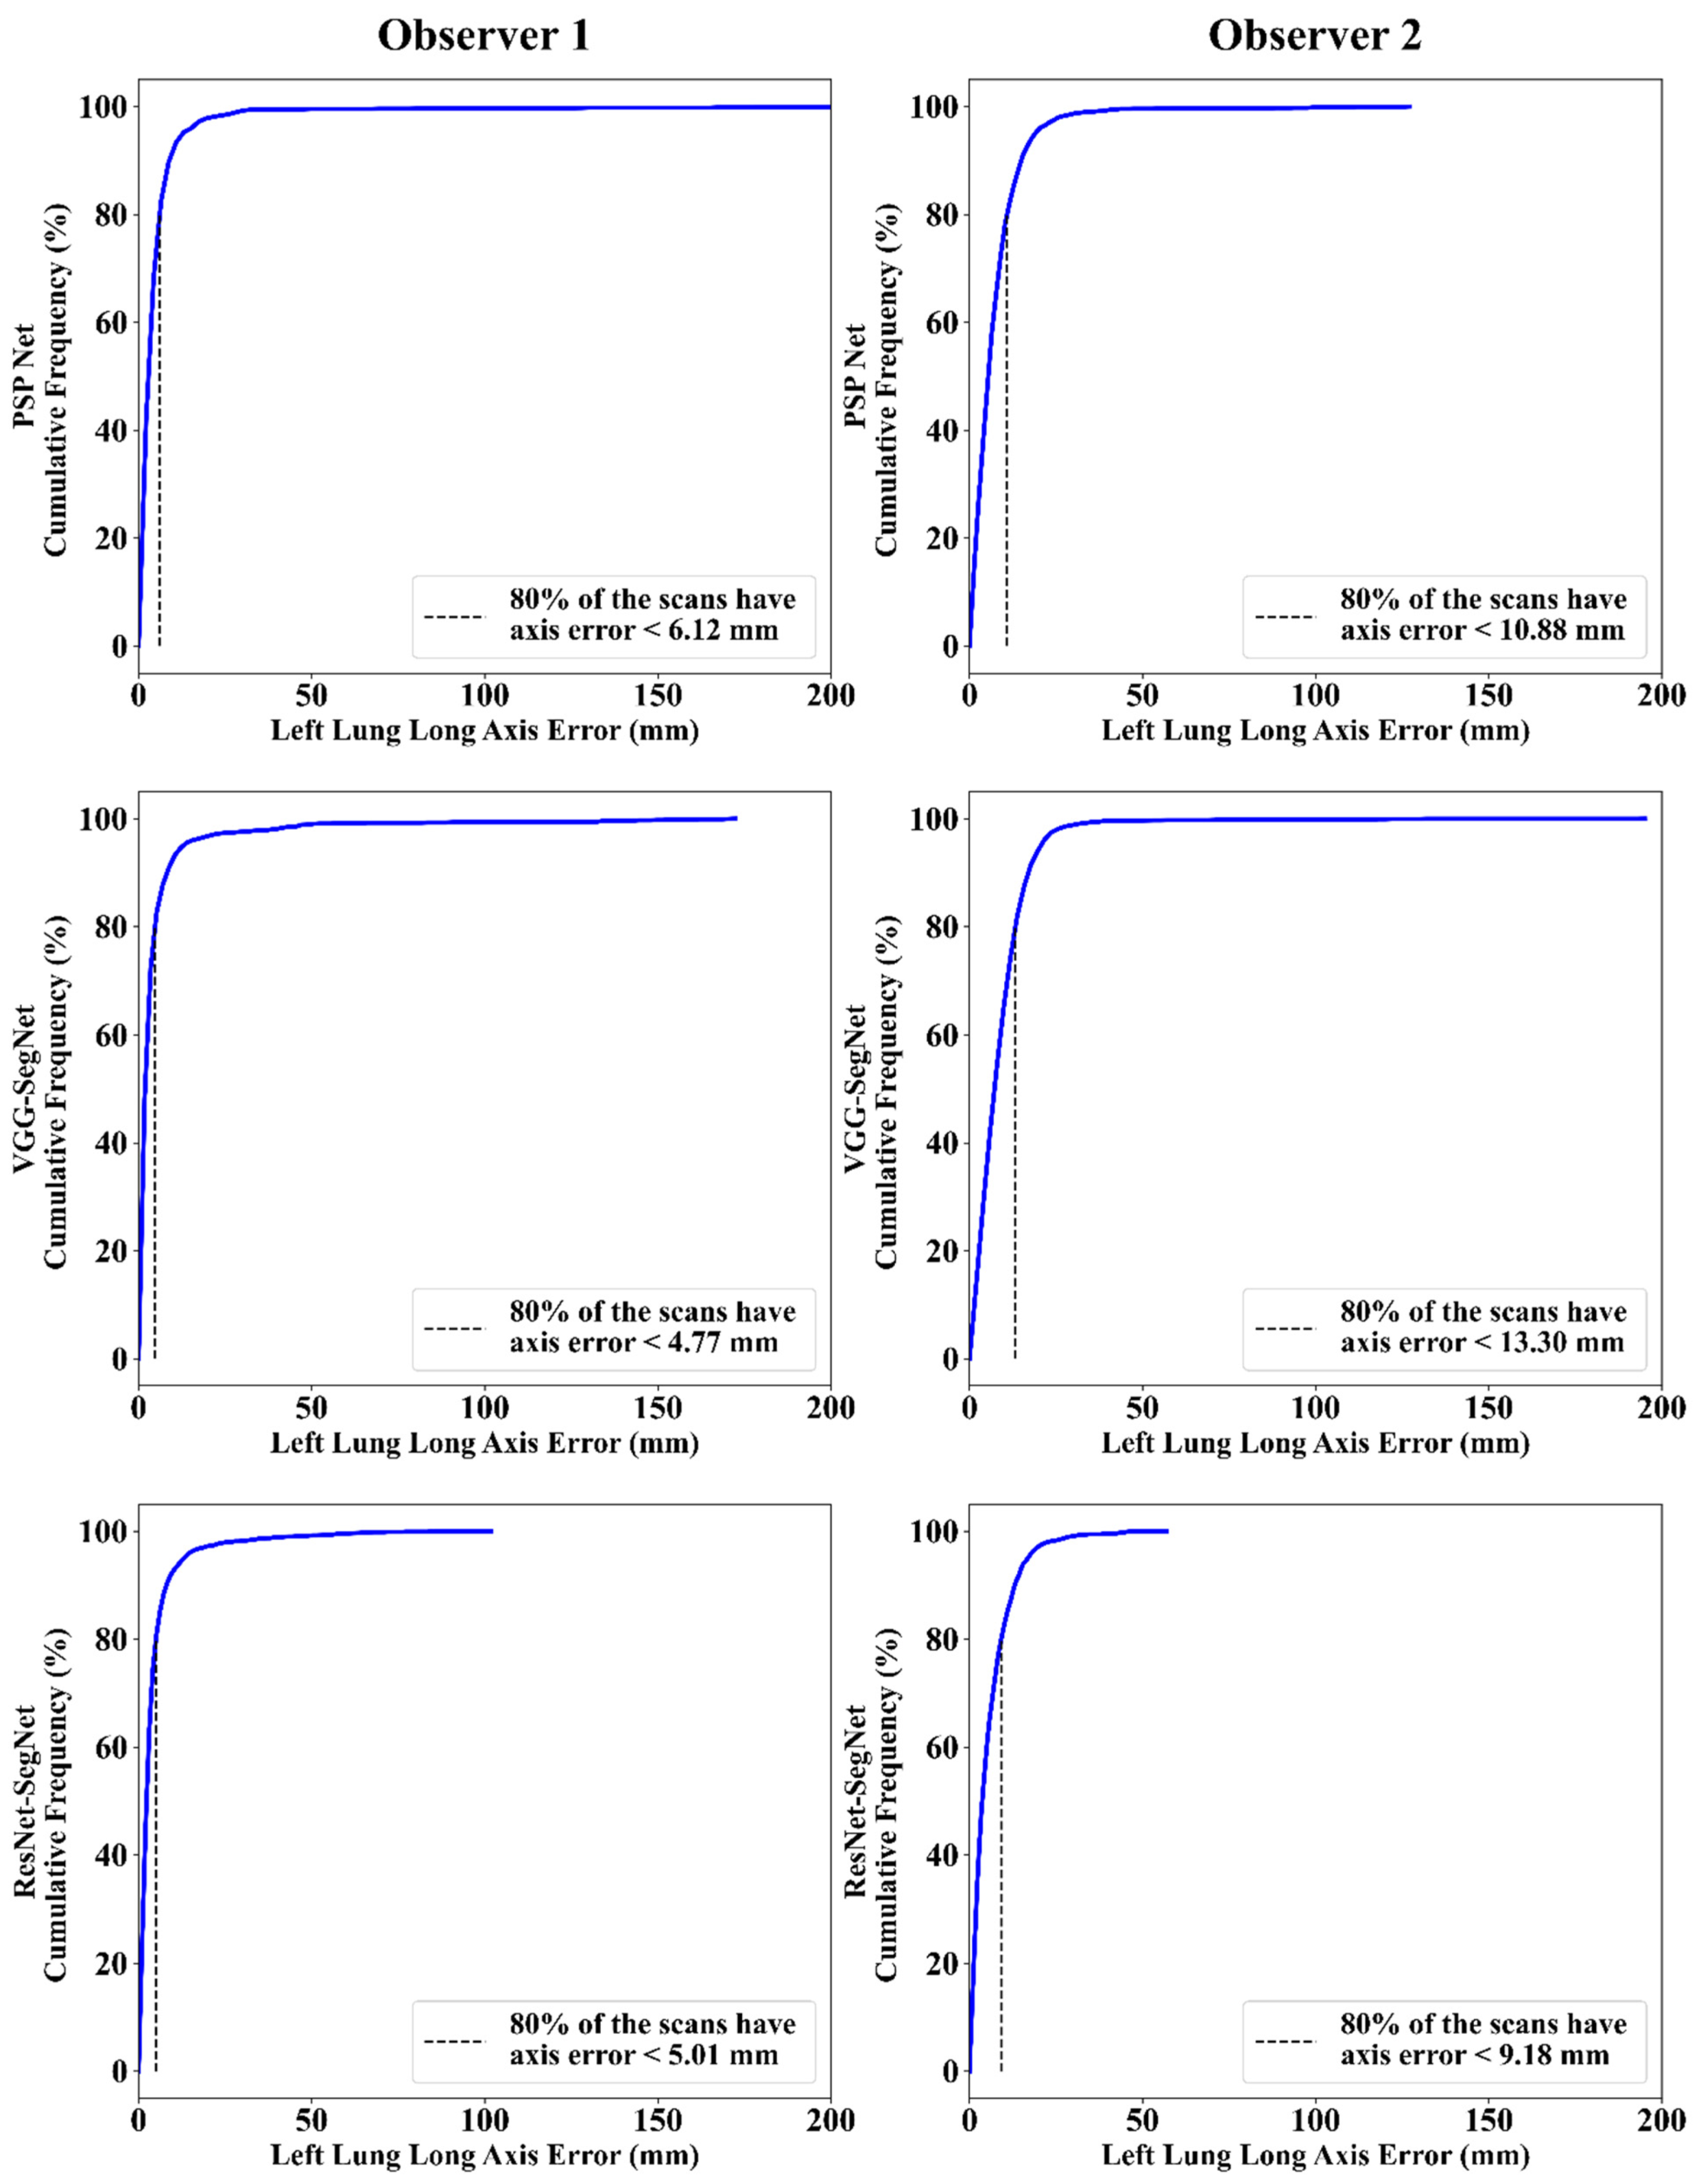

Cumulative Frequency Plot for Lung Long Axis Error

Correlation Plot for Lung Long Axis Error